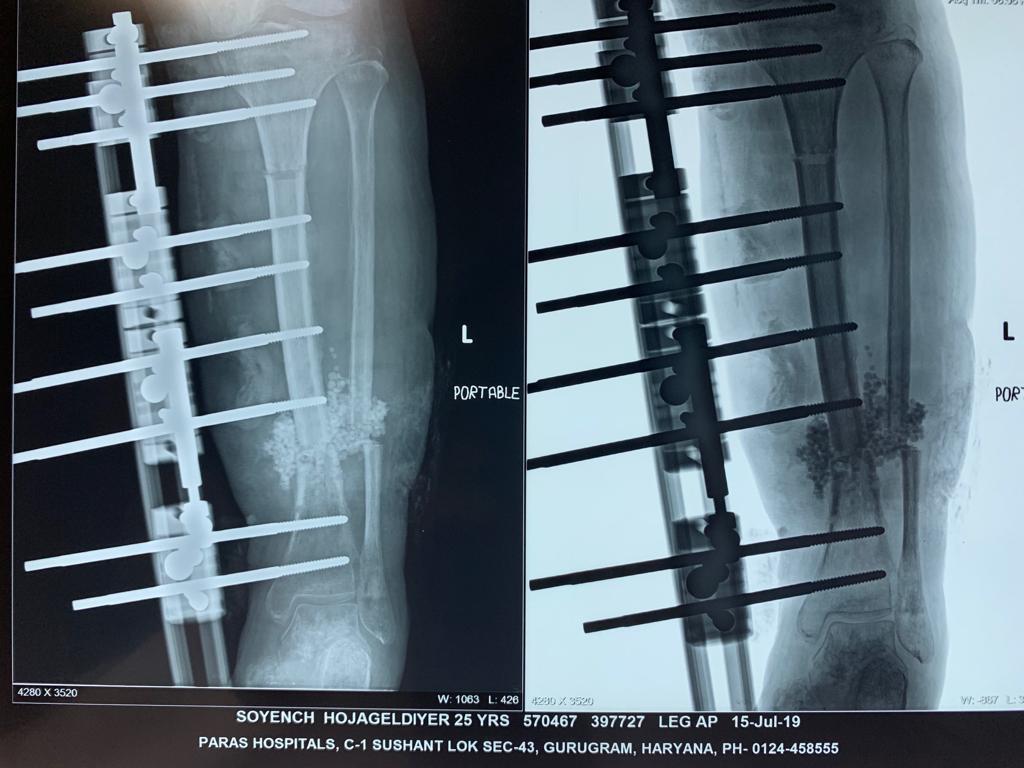

Another common scenario is one in which patient comes to us with open fracture of leg with an ununitied fracture with infection of bone and soft tissue previously elsewhere operated. In such cases the daunting task is to get rid of the infection and heal the fracture; here the technique of distraction osteogenesis (Ilizarov) comes to our rescue. First to get rid of the infection we get a pus culture done to assess the severity of infection and to assess the antibiotics that will be useful. During surgery we remove the dead and infected bone and soft tissues and bring the fracture ends together (docking), and apply the fixator (Monorail). Then we create a cut in the bone (corticotomy) and apply a distraction compression unit to help in creating a gap in the bone to allow distraction osteogenesis. Also antibiotic beads with the sensitive antibiotics are put at fracture site to kill the infection. Gradually over period of weeks the limb get lengthened to normal and infection is healed. The fracture also starts to heal by 3-4 months. The whole process might take upto 6 months.

Below are Xrays of one such case treated successfully by us over a period of 6 months.